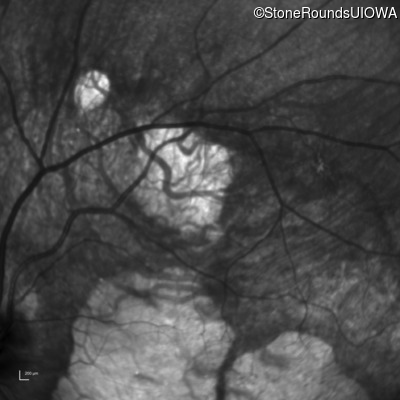

Infrared Fundus Photograph - Left - 20/60 +2 sc

Exemplar